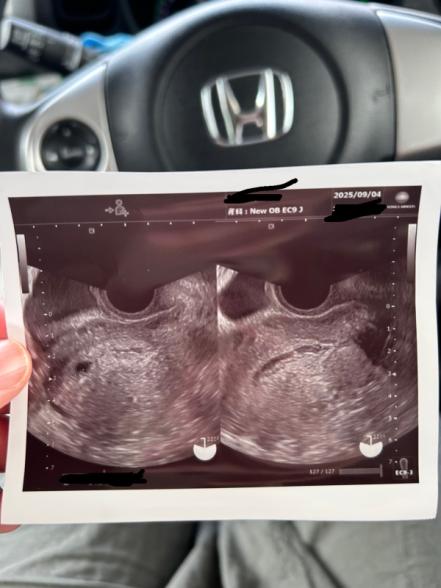

今日9/4に健診に行きました。

最終生理予定日からいくと、5週6日なのですが

胎嚢かわからないと今日言われました。

胎嚢だとしたら、少し小さいかな?と9.8㎜でした。

その横らへんに黒い細長い線があり

血なのか、粘液かなんかかなーということで

妊娠確定といきませんでした。

黒く細長いのがなんなのか、

丸い黒いのは胎嚢なのか、

初回では、判定されにくいのか。